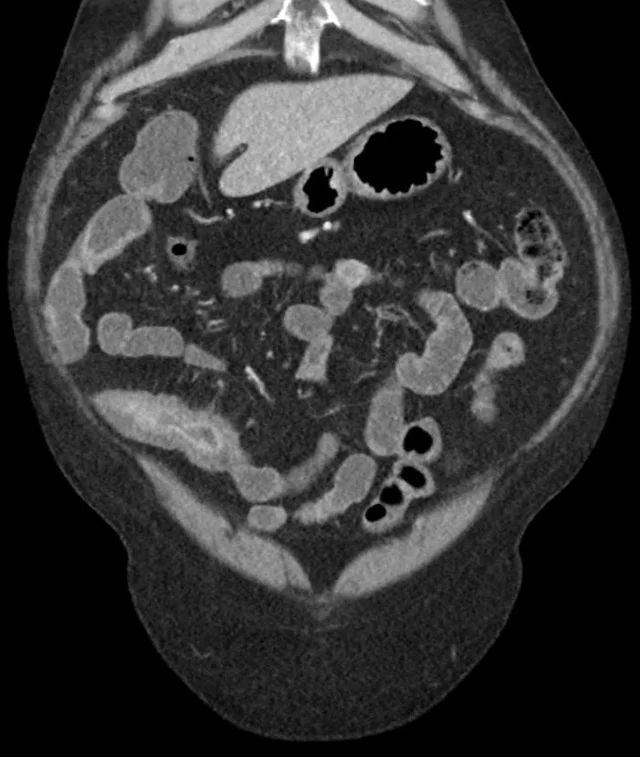

哎呀,说到克罗恩病,这可不是什么轻松的话题。想象一下,你的肚子时不时地闹腾,那种疼痛和不适,真是让人抓狂!但你知道吗?克罗恩病其实是有六大标准的,这些标准就像是一把钥匙,能帮我们更好地了解和面对这个病魔。

首先,得说说“慢性病程”。克罗恩病可不是一时半会儿就能好的,它是个慢性子,可能会伴随你很长时间,甚至一辈子。然后是“透壁性炎症”,这意味着炎症不仅在肠壁表面,还深入到肠壁内部,这可比表面问题严重多了。

再来,“节段性病变”也很关键。你的肠道可能会有一段一段的病变,这些病变区域就像是道路上的坑坑洼洼,让你的肠道运输不畅。而“阿弗他溃疡”则是肠道内的小溃疡,虽然小,但疼起来也是要命的。

别忘了“非干酪性肉芽肿”,这是一种特殊的炎症细胞聚集,听起来挺专业的,但简单说就是肠道里有种不正常的组织。